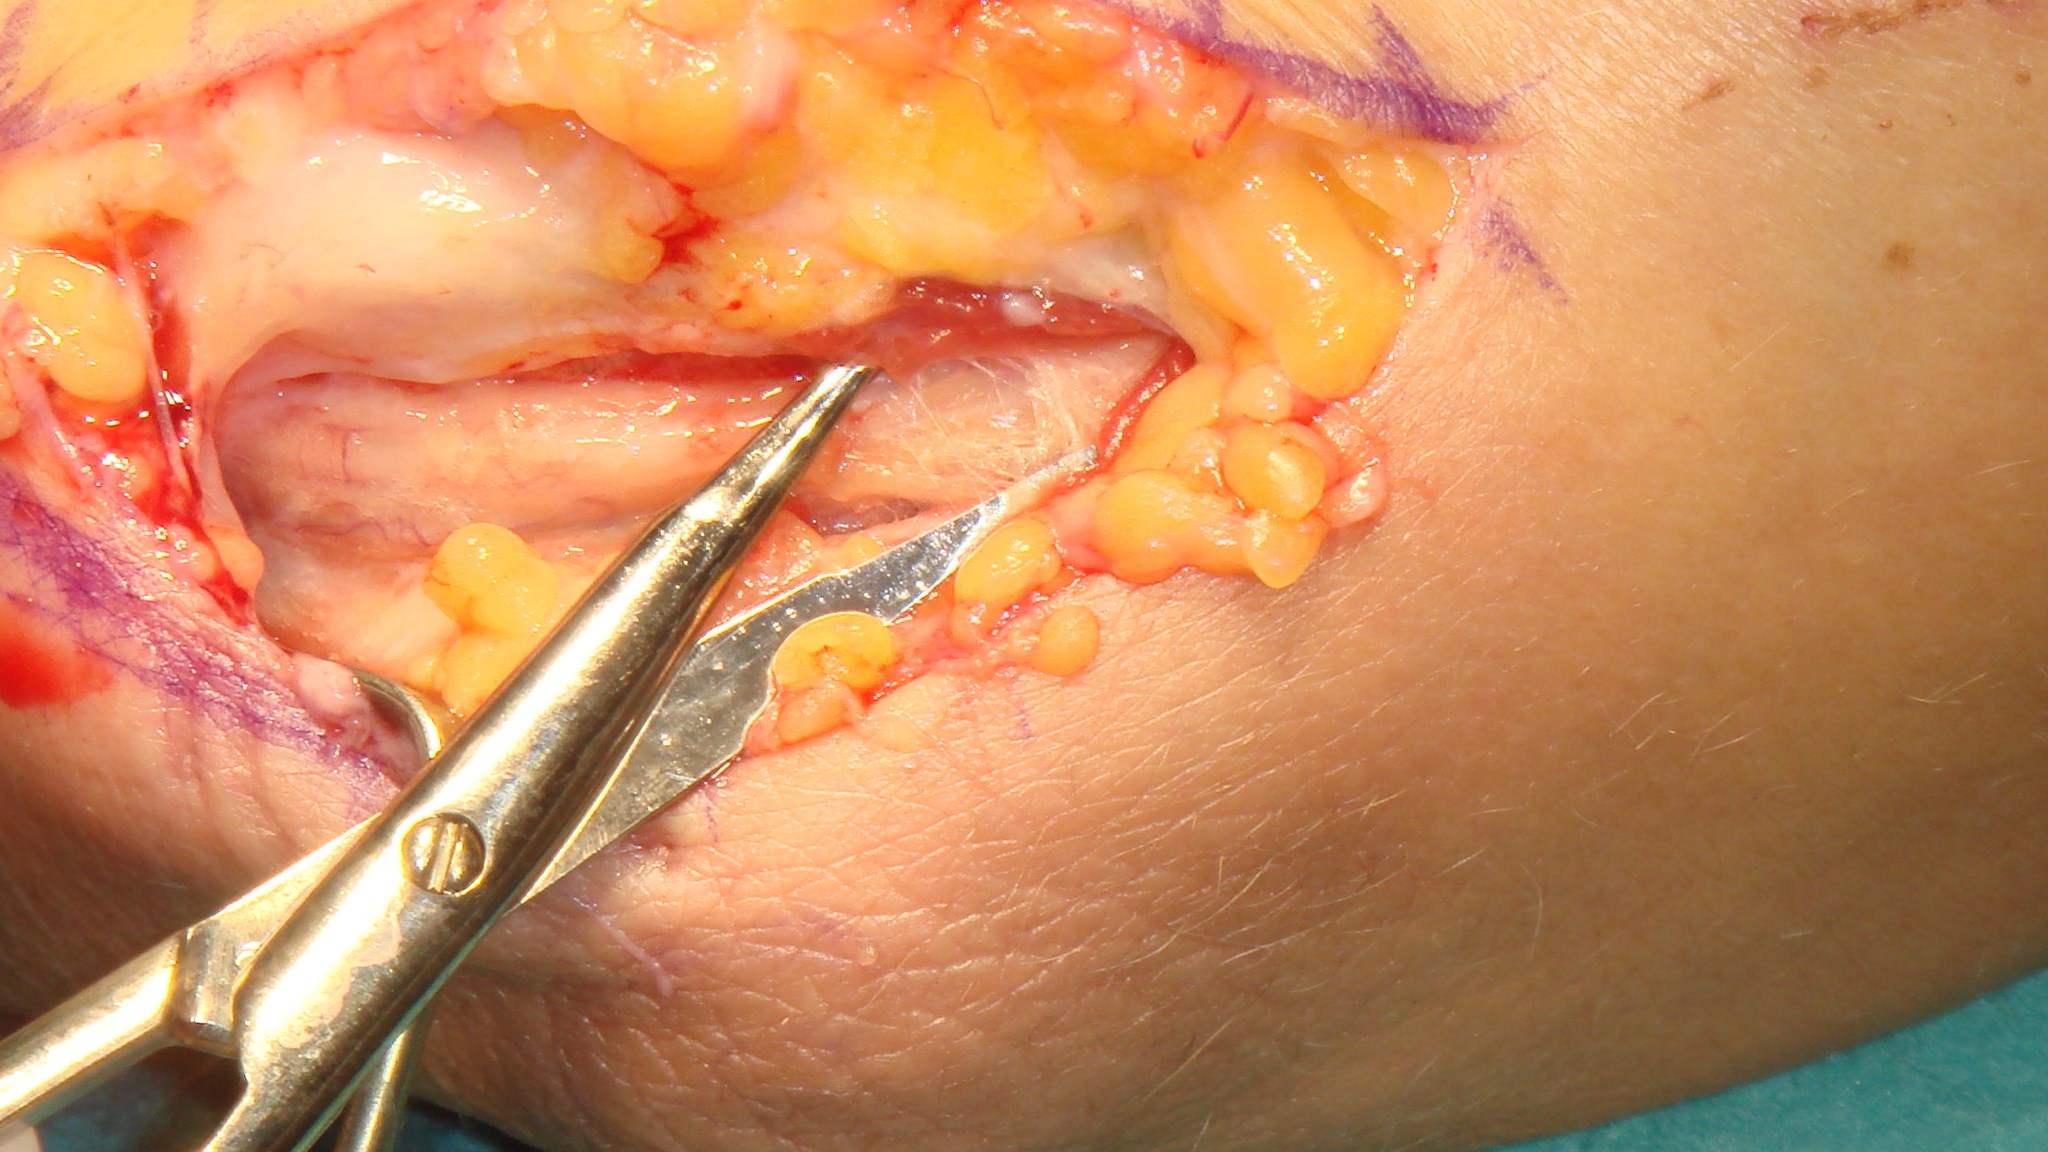

Triggerfinger operation

A1 ligamentet nås genom ett litet snitt i vola, därefter klyvs det med skalpell eller sax. Ligamentet ses längst distalt i såret med ljusreflex.

Undvik att klyva längre distalt om A1 för att förhindra bågsträngsfenomen! (Patienten blev även opererad för karpaltunnelsyndrom, därav snittet i handloven).